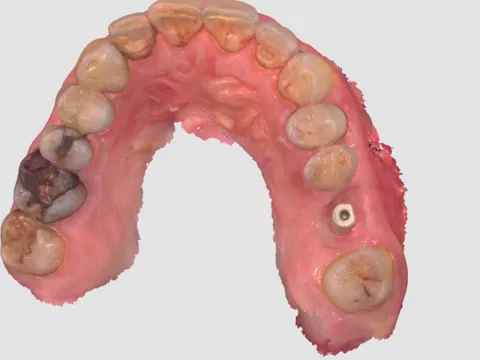

2a. 2b. Initial intraoral view of the molar.

2a

2b